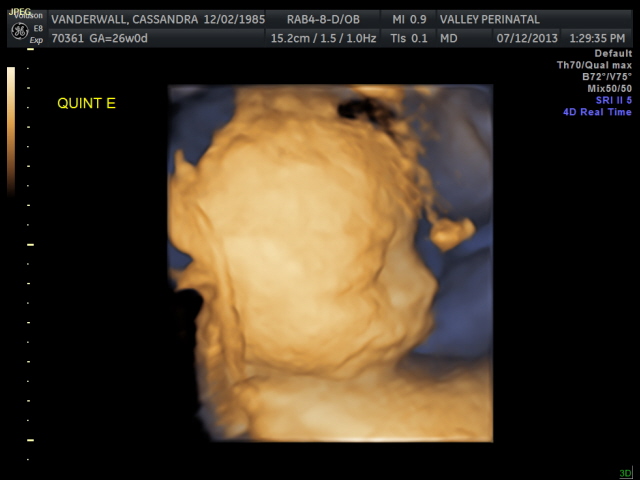

Friday we surpassed yet another milestone! The babies have been cooking for 7 months, which means we are now above the average gestational age for quintuplets. All of the babies were measured on Friday and they are all measuring within a day or two of the recommended size for babies at this point in pregnancy.

The biggest one in the bunch is Baby B at 2lbs and 12oz at the 62nd percentile. Little Elle Rose (Baby E) is the munchkin, but not by much as baby D and Theo (baby A) are also the same weight (2 ½ lbs) but just a bit longer. At this rate, when the baby’s are measured again at 32 weeks they will be about 1lb heavier each. Let’s just hope this Mama can keep up!